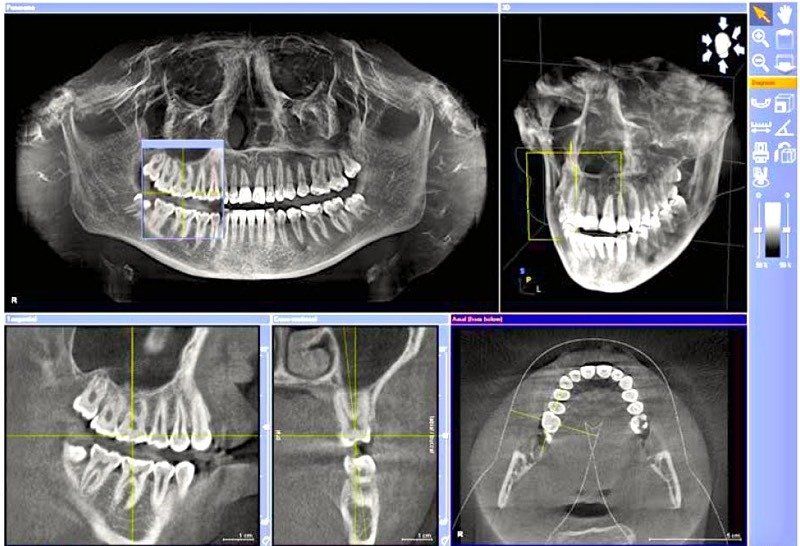

Il Centro di Radiologia Muglia - Rago - Scaletta è dotato di un'apparecchiatura di ultima generazione, il Dentascan Cone Beam 3D, con cui vengono eseguiti:

- esami in 3D delle arcate dentarie;

- studi pre e post implantari;

- studi delle articolazioni temporo-mandibolari e dei seni paranasali.

L’esame consente al dentista una visualizzazione anatomica totale delle arcate dentarie e delle strutture del distretto maxillo-facciale nei vari piani ortogonali.

Il Dentascan Cone Beam 3D sottopone il paziente a basse dosi di radiazioni, inferiori rispetto alla tac convenzionale: ciò è importante nel caso di ripetuti controlli e in pediatria, dove si applicano specifici programmi che riducono ulteriormente la dose di radiazioni.